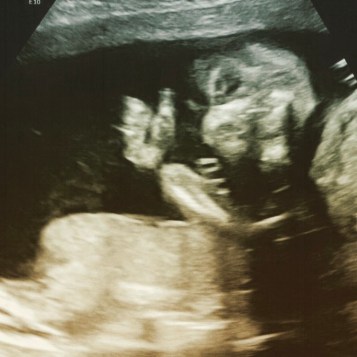

We hebben begin Januari de 20 weken echo gehad. We hadden een uitgebreide echo waar alles bekeken werd. Het was allemaal goed en de kleine lag in de curve qua groei dus dat was heel fijn om te horen. Inmiddels weten we ook dat we een meisje krijgen!! Yaaaaaay!!! Het is superleuk om te weten wat het wordt en nu kan je ook meer gericht kijken naar dingen voor het kamertje, kleertjes enz. De naam is ook een stuk makkelijker, die houden we nog wel ff geheim haha.

img_0824

Thumbs up ❤

It’s the 20th of January already and we’ve had the 20th week ultrasound on the 4th, we can’t wait to meet our little jellybean 😀

During the ultrasound the sonographer looked if there where any abnormalities but there was nothing to see, yay!  The little one was growing normally so thats good to, and we know it’s a girl!! Yaaaaaay!!! We are so happy to know it’s a girl and we can’t wait to meet her. Now we can look more specific for thing in her room, clothes etc.. Choosing the name became 50% more easy haha, but we will keep that a secret till she’s born.